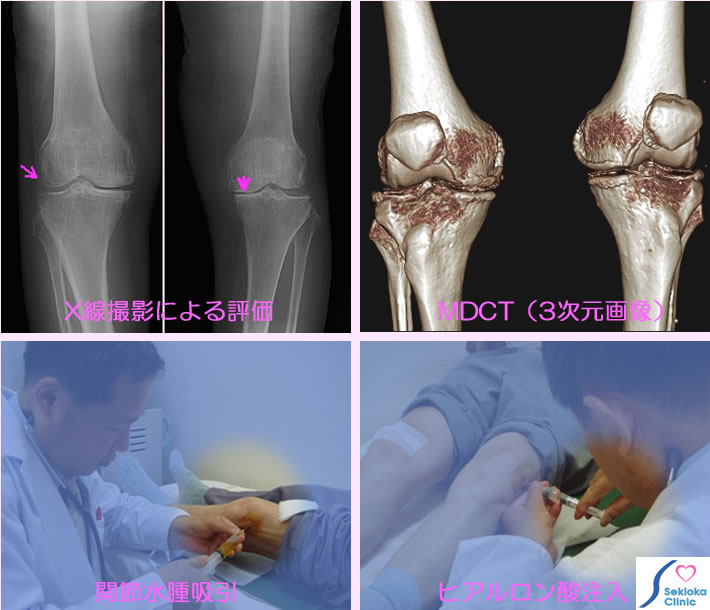

| 診断 | 膝の視診と触診でもほぼ診断できますが、病気の程度・進行度の評価のためX線撮影を行います(上段左の画像)。関節軟骨の減少によって関節裂隙が狭くなる、軟骨部の石灰化、骨棘(余分なとがり)などを認めます。上段右はMDCT3次元画像で、石灰化、関節の狭小化などよくわかりますが 変形性関節症のみの疑い時は通常検査には使いません。 |

| 治療 | 関節に水が貯まっている時(触診でほぼわかる)は排出後、ヒアルロン酸を注入(下段右写真)します。この注射を週に1回、5週間ほど続けます。当院でヒアルロン酸注射は既に130名以上の方が受けておられるが約8割の方に痛みの消失、軽減が見られる。他に運動療法や痛み止めを併用することもあります。 |